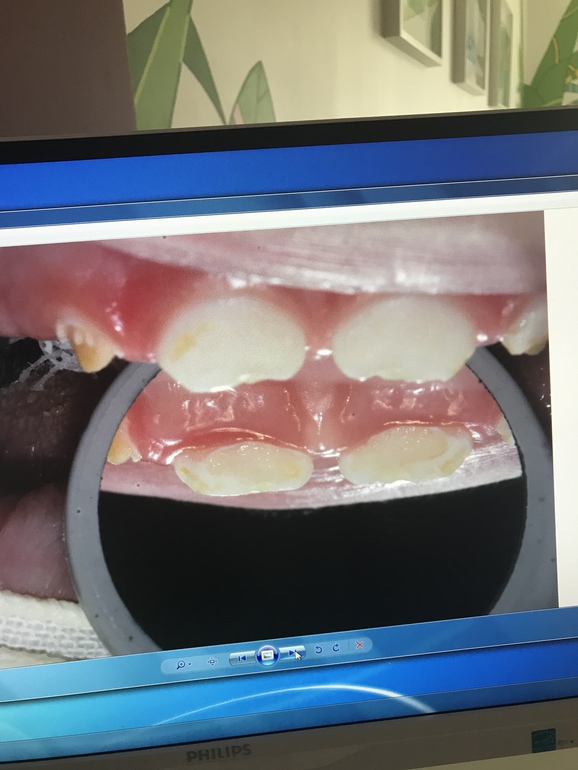

Вчера вылечили и реставрировали зубы младшему. 4 зуба из 6... 2 часа под Севоран. Спасибо огромное врачам клиники Ваш Стоматолог они умнички и проделали колоссальную работу! У сына были 2 пульпита и кариес на передних верхних резцах. Обошлось лечение в 33.500₽ . Теперь ребёнок опять может без дискомфорта есть холодное/горячие / кислое / твёрдое ! наркоз перенесли хорошо , в пятницу едем на осмотр после операционный ! Для тех кому интересно приложу фото до и после

Зубки конечно ещё будут реставрироваться по необходимости